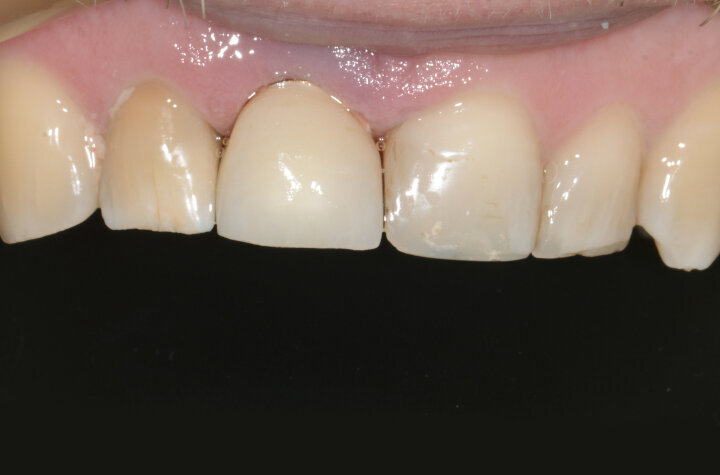

The aim of this article is to present a case of single-tooth prosthetic restoration in the aesthetic zone step by step. The patient was referred to our clinic with a fractured root of tooth #11 (Fig. 1). The cone beam computed tomography (CBCT) analysis confirmed the fracture and revealed external resorption of the root from the vestibular side (Fig. 2). The tooth had to be extracted, and it was decided to follow immediate implant placement with a temporary aesthetic implant restoration. The immediate implant placement was planned with short-term non-occlusal loading.

Fig. 1: Situation before treatment, which led to the decision to extract tooth #11.